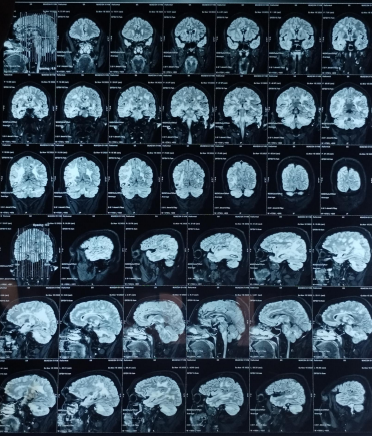

Early-onset dementia (onset before age 65) is a thought-provoking ailment with many possible causes, including early-onset familial Alzheimer’s disease, frontotemporal lobar degeneration, Parkinson’s dementia, Lewy body dementia, disorders of amino acid and organic acid metabolism, leukodystrophies, lysosomal storage diseases, disorders of metal metabolism, and mitochondrial diseases [6]. In our patient, the history, physical examination, laboratory investigations, and neuroimaging were not suggestive of these causes and prompted the search for a rare etiology. The most common MRI finding associated with CADASIL is basal ganglia and white matter hyperintensities in T2-weighted sequences that start as punctate or nodular foci and then often become confluent, extensive, and usually symmetrical, mainly in the periventricular region, anterior temporal pole, external capsule, the centrum semiovale, and frontal and parietal areas. In our patient, diagnosis was made mainly from MRI findings as seen in fig. 1, 2.

Fig. 1: Tiny petechial hemorrhages are seen in bilateral basal ganglia, white matter of both cerebral hemisphere, midbrain, pns and cerebellum. Diffuse cerebral and cerebellar atrophy is seen with enlarged ventricle due to atrophy. Acute to subacute parenchymal bleed is seen in righttemporo–occipital region. minimal intraventricular leakage of blood is also seen in 4th ventricle